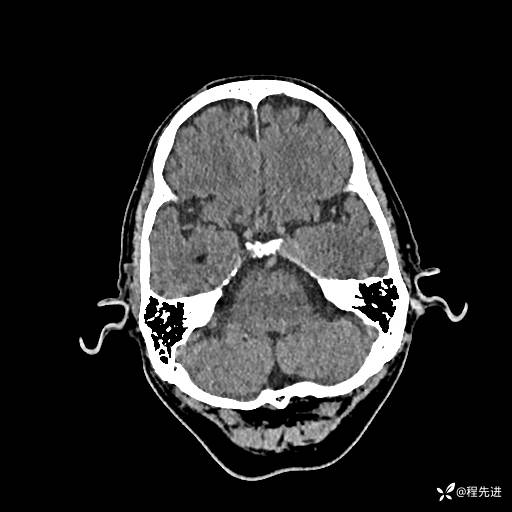

患者性别:男

患者年龄:74岁

简要病史:出现视物重影2月余,未予重视,2月来症状逐渐加重

实验室检查:无特殊

CT平扫: